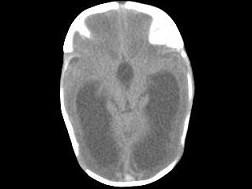

问题 1岁,女,头颅呈球状,颅骨透光试验阳性,请结合CT图片,选择最可能的诊断 ( )

选项 A、先天性脑积水 B、重度脑积水 C、慢性双侧性巨大硬膜下血肿 D、水瘤 E、脑严重缺血

答案 A